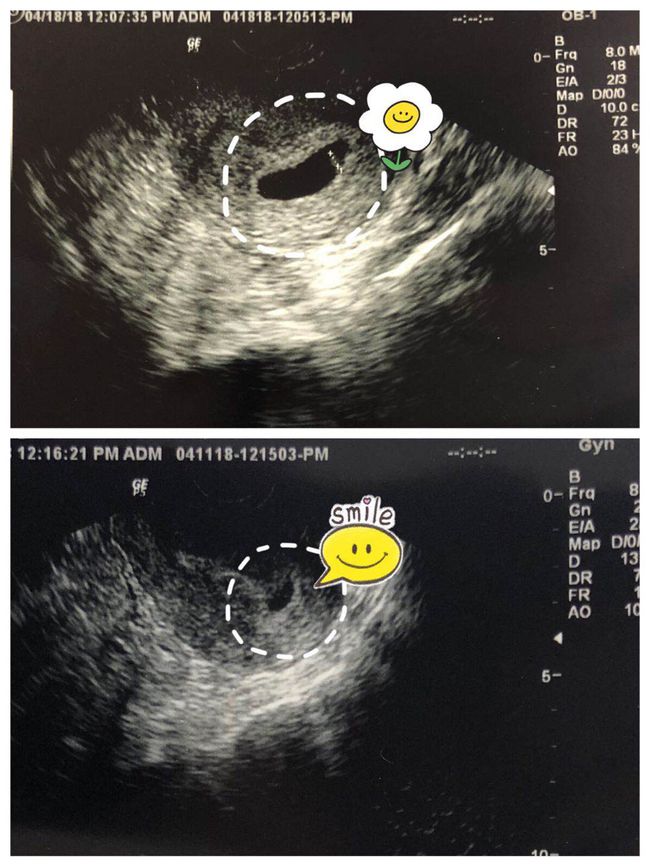

超声检查:确定孕周、胎位、胎儿数量等基本信息。

超声检查:观察胎儿生长发育情况,检查胎儿有无畸形。

超声检查:复查胎儿生长发育情况,观察胎儿有无畸形。